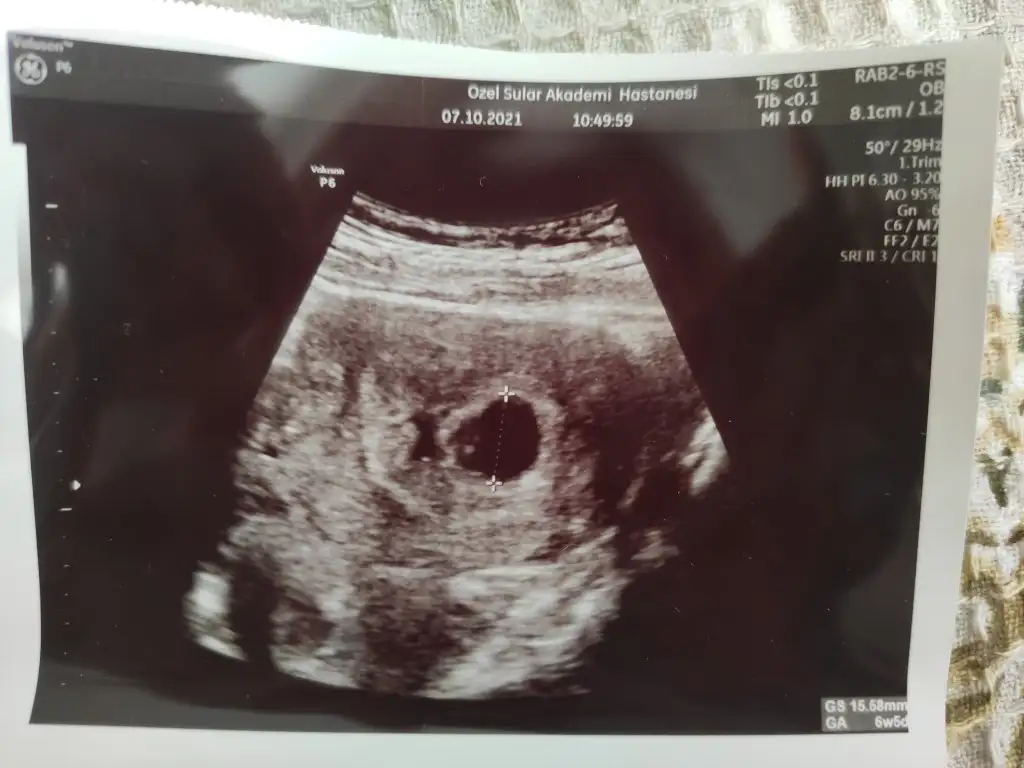

Benimki 6+1 bu şekilde canımKızlar 6+4 ve yakınlarında gidip ultrason görüntüsü aldıysanız bir paylaşabilir misiniz rica etsem

Teşekkür ederim Peki kalp atışı duymuş muydun bu ultrasonda?Benimki 6+1 bu şekilde canım